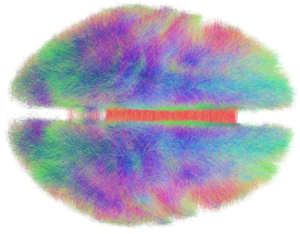

الكونكتوم connectome ( []kəˈnɛktoʊm[])، هي خريطة شاملة للوصلات العصبية في المخ، ويمكن النظر فيها "كمخطط تشبيك" لها. بشكل أكثر شمولاً، تشمل الكونكتوم رسم خريطة لجميع الوصلات العصبية في الجهاز العصبي للعضيات.

إنتاج ودراسة خرائط الكونكتوم، المعروفة بالكونكتومية، يمكن ترتيبها في مقياس من الخريطة المفصلة لجموعة العصبونات والتشابكات العصبية في الجهاز العصبي للعضيات أو جزء منه لوصف واسع النطاق للربط الوظيفي والهيكلي بين جميع مناطق البنى القشرية وتحت القشرية. يستخدم مصطلح "الكونكتوم" بصفة رئيسية في الجهود العلمية لتصوير، رسم خريطة، وفهم تنظيم التداخلات العصبية في المخ.

الهدف النهائي للكونكتومات هو رسم خريطة للمخ البشري. يتم هذا الجهد من خلال مشروع الكونكتوم البشرية، برعاية المعاهد الوطنية للصحة، الذي يركز على بناء خريطة شبكية للمخ البشري لدى البالغين الأصحاء.